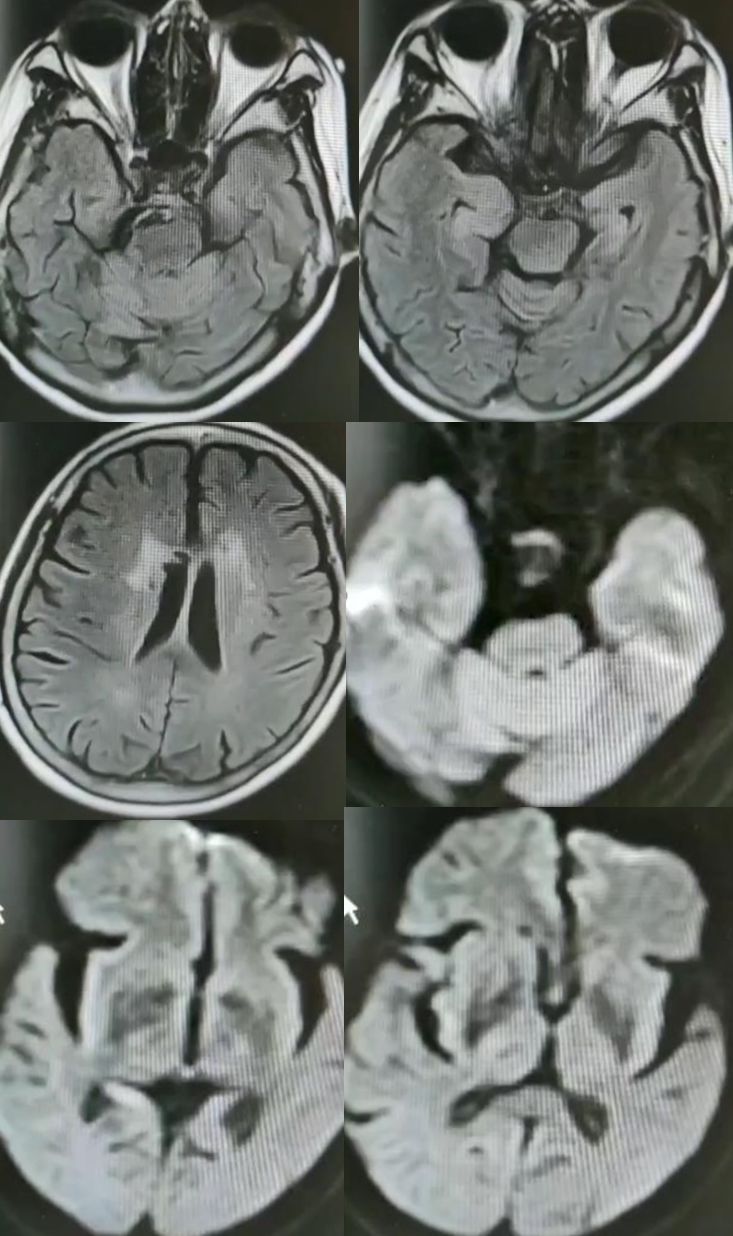

30岁女性,言语不清3年。

答案:肝豆状核变性。又称Wilson’病(WD),是一种常染色体隐性遗传的铜代谢障碍性疾病。主要是由于铜离子异常大量沉积于肝、脑、肾等组织,从而导致全身多系统多器官的损害,以神经系统症状、精神症状、眼部损害、肝脏损害等为主。神经系统最突出的症状是锥体外系症状,包括震颤、构音障碍、肌张力障碍、手足徐动症、共济失调等。构音障碍表现为声音低沉、含糊或嘶哑、缓慢或断续,严重时发不出声,是舌、唇、咽、喉和下颌肌肌张力增高所致。而肝脏的表现通常为肝功能损害、肝硬化、门脉高压症等,一般年轻患者居多。MRI表现为壳核、尾状核头和苍白球在T2WI上呈低信号,齿状核和红核亦可见T2WI为低信号。还可有不同程度的脑萎缩,如两侧壳核对称性裂隙,豆状核、尾状核、大脑皮质、脑干和小脑的萎缩。大小熊猫征为Wilson病的典型特征。